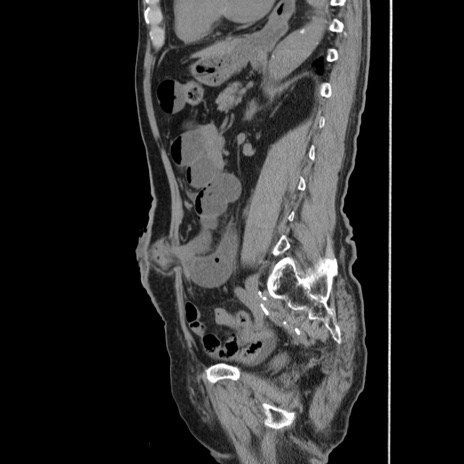

症例24(矢状断像)

【症例】80歳代男性

【主訴】左側腹部痛、嘔吐

【現病歴】本日早朝より左腹部に痛みあり。昼頃嘔吐認めたため、救急要請。

【既往歴】直腸癌(Mile手術)、胆摘

【身体所見】意識清明、BT 35.9℃、BP 221/93mmHg、SpO2 97%(RA) 、腹部:左ストーマ周囲に限局性の腹部膨隆あり。 膨隆部自発痛・圧痛あり・軟。

【データ】WBC 7700、CRP 0.09